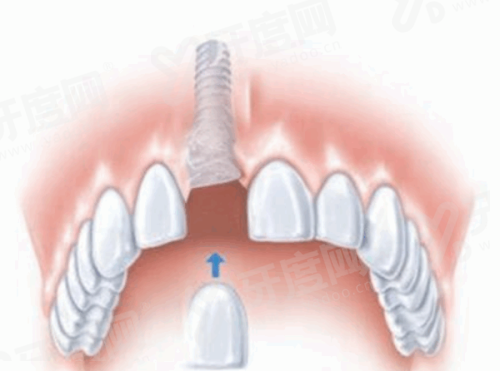

√ 种植牙的过程一般包括植入种植体、骨愈合、安装愈合基台、取模制作牙冠等步骤,整个过程需数月至半年不等,具体根据患者愈合情况而定。

√ 士卓曼适用于单颗牙缺失、多颗牙缺失乃至全口无牙颌的修复,同时,士卓曼提供多样化的修复组件,确保修复成效既美观又功能性强。